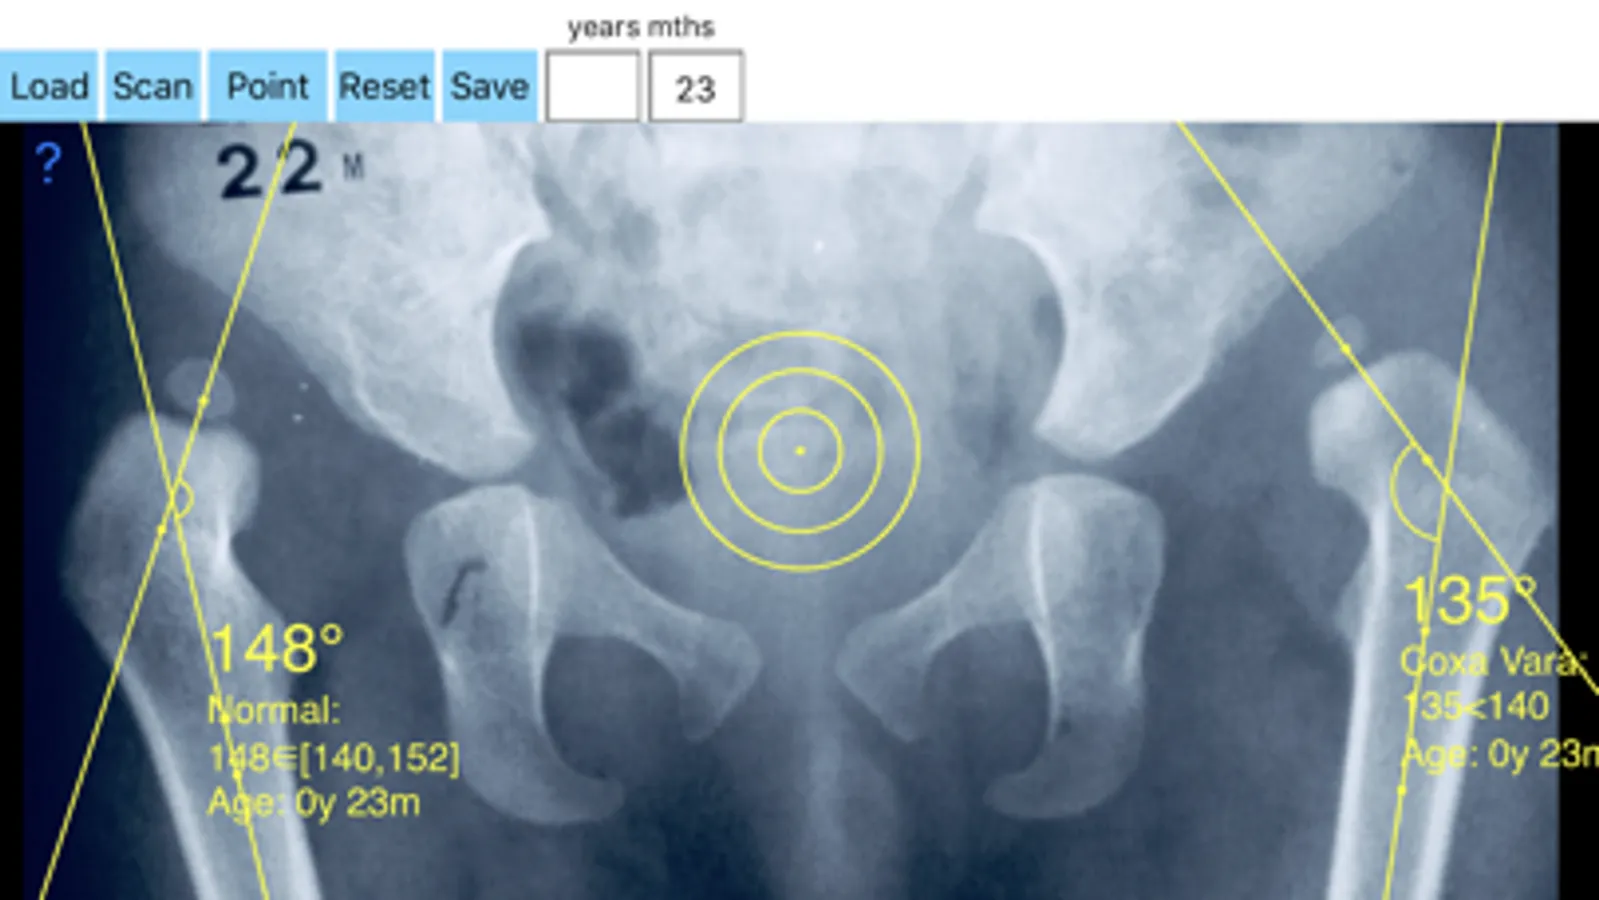

-Offers a very convenient way to determine the most accurate possibly lines in order to measure the angle. By the aid of a circular template, four points of interest are marked. The automatically formed lines drawn between points give an angle which is measured automatically by the App. The visualized results are in degrees.

By inputing the age of the patient in the App, the measured angle is compared with values from normal reference database (see reference) according the patient age. In case the measured angle is increased or decreased, the hip is valgus or varus respectively.